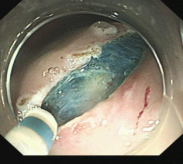

胃窦的腺癌 行ESD治疗

术中见较粗穿支血管,裸化后凝除,最终高效、安全的切除病灶。

结肠腺瘤的ESD手术

十二指肠溃疡降段早癌的内镜粘膜剥离手术治疗(ESD)

直肠巨大侧向发育型肿瘤,内镜下完整切除(ESD),术后病理证实粘膜内癌,不需追加治疗,达到治愈目的,保留正常器官,避免外科手术。

胃内4x4cm粘膜下隆起,胃镜下完整切除(ESE),术后病理证实平滑肌瘤,保留胃正常组织结构。

内镜手术展示